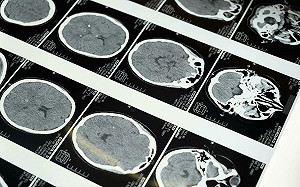

比米粒還小的鼠腦! 繪出史上最精細3D腦圖 科學家打造神經連結「宇宙地圖」